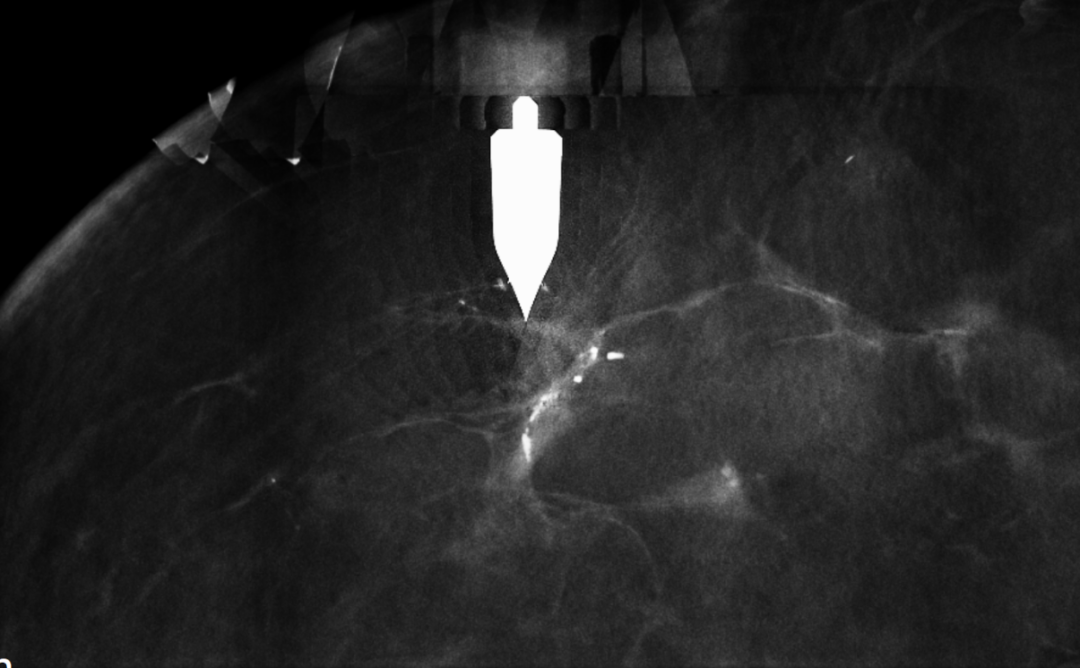

计算坐标,实现三维空间“零误差”定位

在清晰成像的基础上,计算机会自动计算钙化灶等病灶的三维坐标。医生在局部麻醉后,按照断层影像的引导,将一根细如发丝的定位钩针精准插入病灶附近。

怎么制造手术钩针狙击乳腺结节癌变!这种新技术专揪早期乳腺癌_https://www.jmylbn.com_新闻资讯_第7张

▲钩针精准定位释放于病灶区域

钩针末端的倒钩会固定在病灶周围组织中,从而为外科医生标记出病灶的准确位置。整个定位过程误差可控制在毫米级。

患者随后带着这根“导航针”进入手术室,外科医生便能据此快速、精准地找到并切除目标病灶。